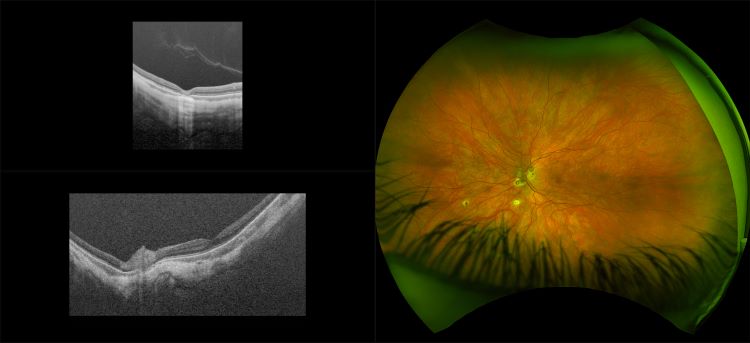

Monaco - Pigment Epithelial Detachment, RG, OCT